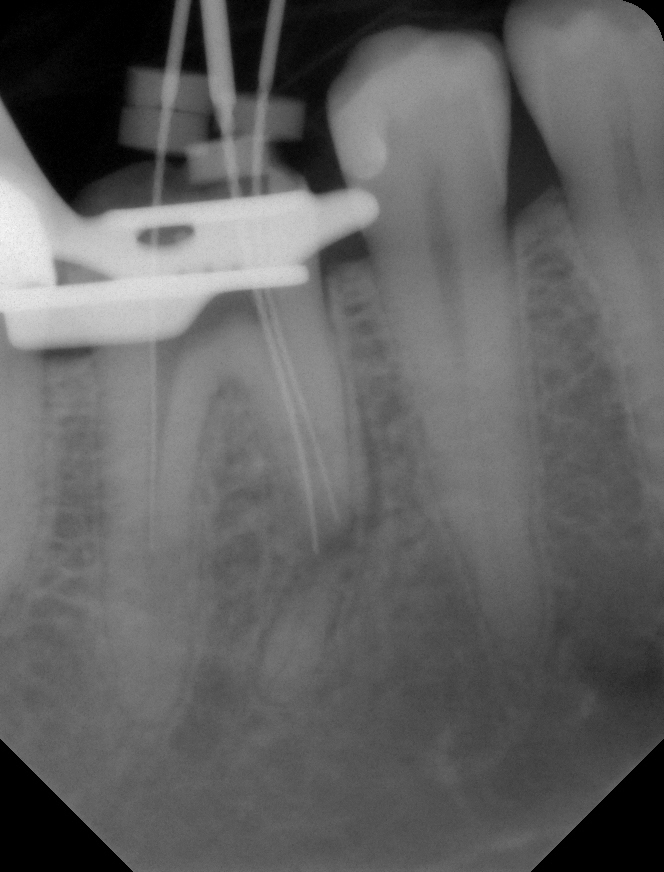

05 – Zahn 46 – Kontrastaufnahme mit Instrumenten auf elektrometrisch bestimmter AL Veröffentlicht 2. Juli 2013 am 664 × 872 in Wurzelresorption mal anders